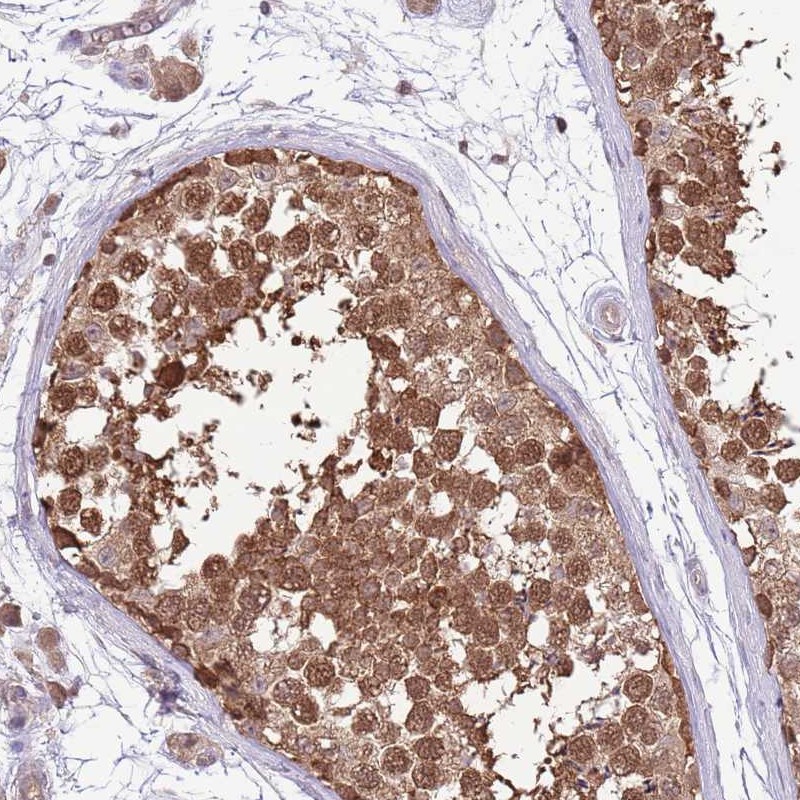

Immunohistochemical staining of human testis shows strong cytoplasmic and nuclear positivity in cells in seminiferus ducts.